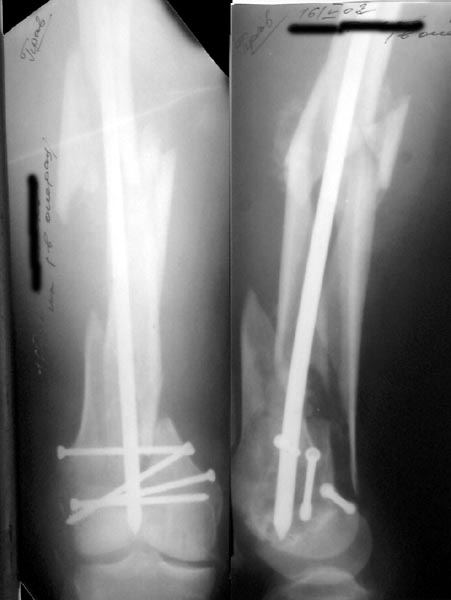

Re: Многооскольчатое бедро

Alexander Chelnokov 16 Май 2002, 17:30

Нету у нас (пока?) гвоздей для ретроградного введения. Доводилось слышать, что можно любые гвозди вводить ретроградно, но как-то не

получается пока преодолеть психологический барьер. В основном потому, что не могу для себя уяснить преимущества введения через колено

обычного UFN. Или, как коллеги из Индии рассказывали, кое-кто вводит UTN в бедро ретроградно.

ЛА> и увеличенным количеством винтов дистально или как ты любишь miss

ЛА> a nail.

Да, примерно так и сделали. Надо было, пожалуй, кончик гвоздя еще спилить, чтобы отверстие было еще дистальнее. Англоязычные коллеги еще

советовали винты в передне-заднем направлении вводить, но что-то не увидел, где там подходящее место.